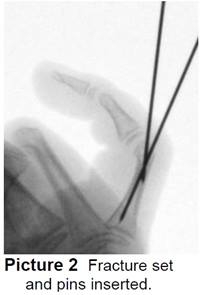

- The surgeon will do a closed reduction and/or pinning. Pins are pushed into the skin to hold the pieces of bone together until the they heal (Picture 2). The ends of the pins on the outside of the skin are bent (Picture 3).